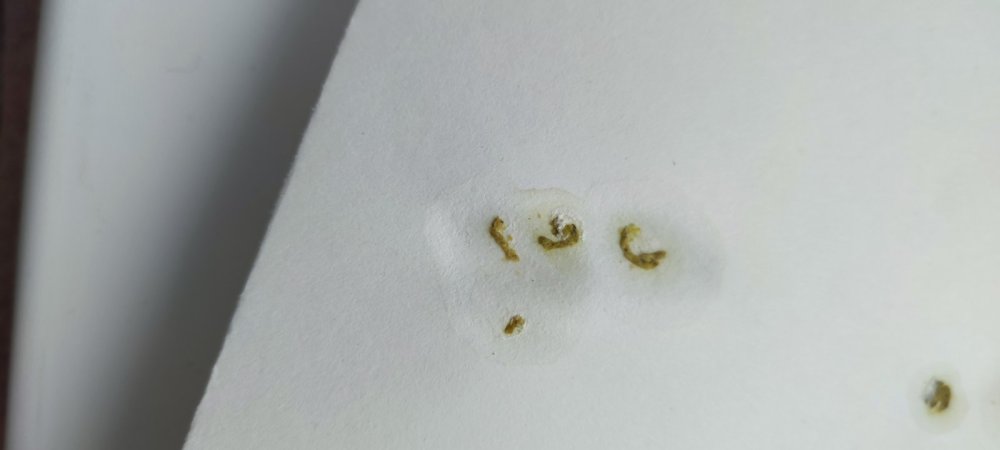

Здравствуйте! Вчера не смог ночью пройти мимо белого голубя (скорее всего метис) сидевшего на плите на улице, взял его в квартиру, сейчас он находится в переноске. Сделал фото сегодняшнего помета, с глистами. Что можно подавать и как? Внешне других заболеваний не обнаружил. Как принес, после часа дал 2мл воды с растолчённым углем активированным 1/2 таблетки из шприца. Сегодня он чувствует намного лучше. Чем лучше проглистогонить и как?